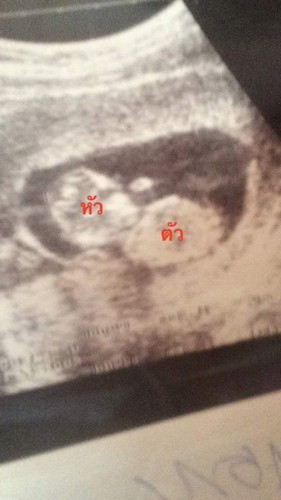

แม่ๆคนไหนดูออกบ้างคะ บ้านนี่ยัง งง อยู่เลย😂

ดูออกค่ะ ศีรษะ ลำตัวและแขนค่ะ😊

ตรงกลางนั้นคือแขนและมือค่ะ อีกสักระยะก็จะค่อยเปลี่ยนจนสังเกตุเห็นนิ้วมือทั้ง5นิ้วค่ะ